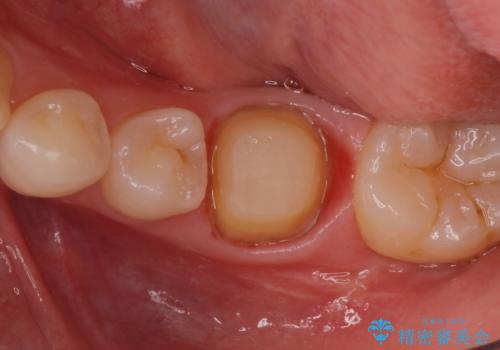

被せ物が入りました。

根管治療が終わった歯は被せ物を装着しないと細菌が根管内に侵入し根の再発のリスクが増えるため早急に被せ物を入れる事をお勧めします。